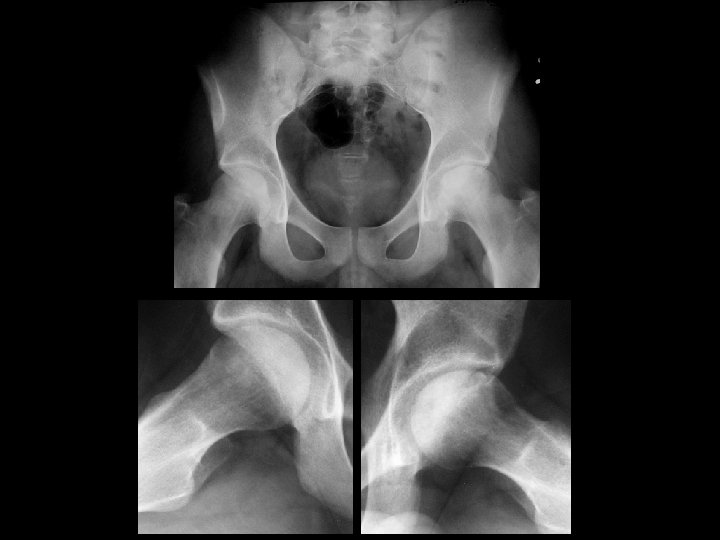

Asymmetric SI fusion • Findings: – Right SI joint fusion – Symmetric hip joint narrowing • ddx: (asymmetric) – Reiter syndrome – Psoriatic arthritis – Infection (symmetric) – Inflammatory bowel dz – Ankylosing spondylitis

Symmertic sacroiliitis & Ulcerative colitis • Findings: – Symmetric SI joint erosion and subchondral sclerosis = sacroiliitis – Mildly dilated ahaustral ascending colon • ddx: – NONE! – This is an Aunt Minnie!